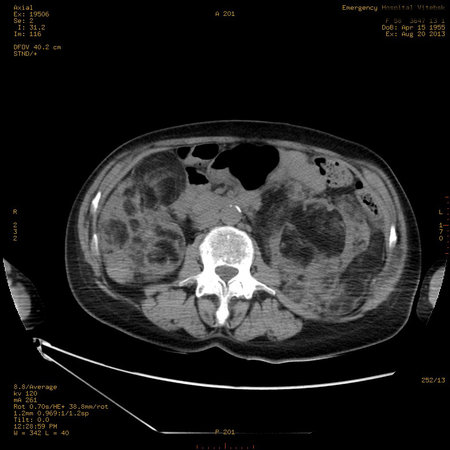

УЗИ почек - туберозный склероз

Пожилая женщина с нормальными мочевиной и креатинином.

Ангиомиолипоматоз почек , думаю компонент туберозного склероза.

Да, туберозный склероз.

Случай консультирован на кафедре радиологии Католического университета г.Лёвен (Бельгия) - зав каф. профессор Р.Оуен.